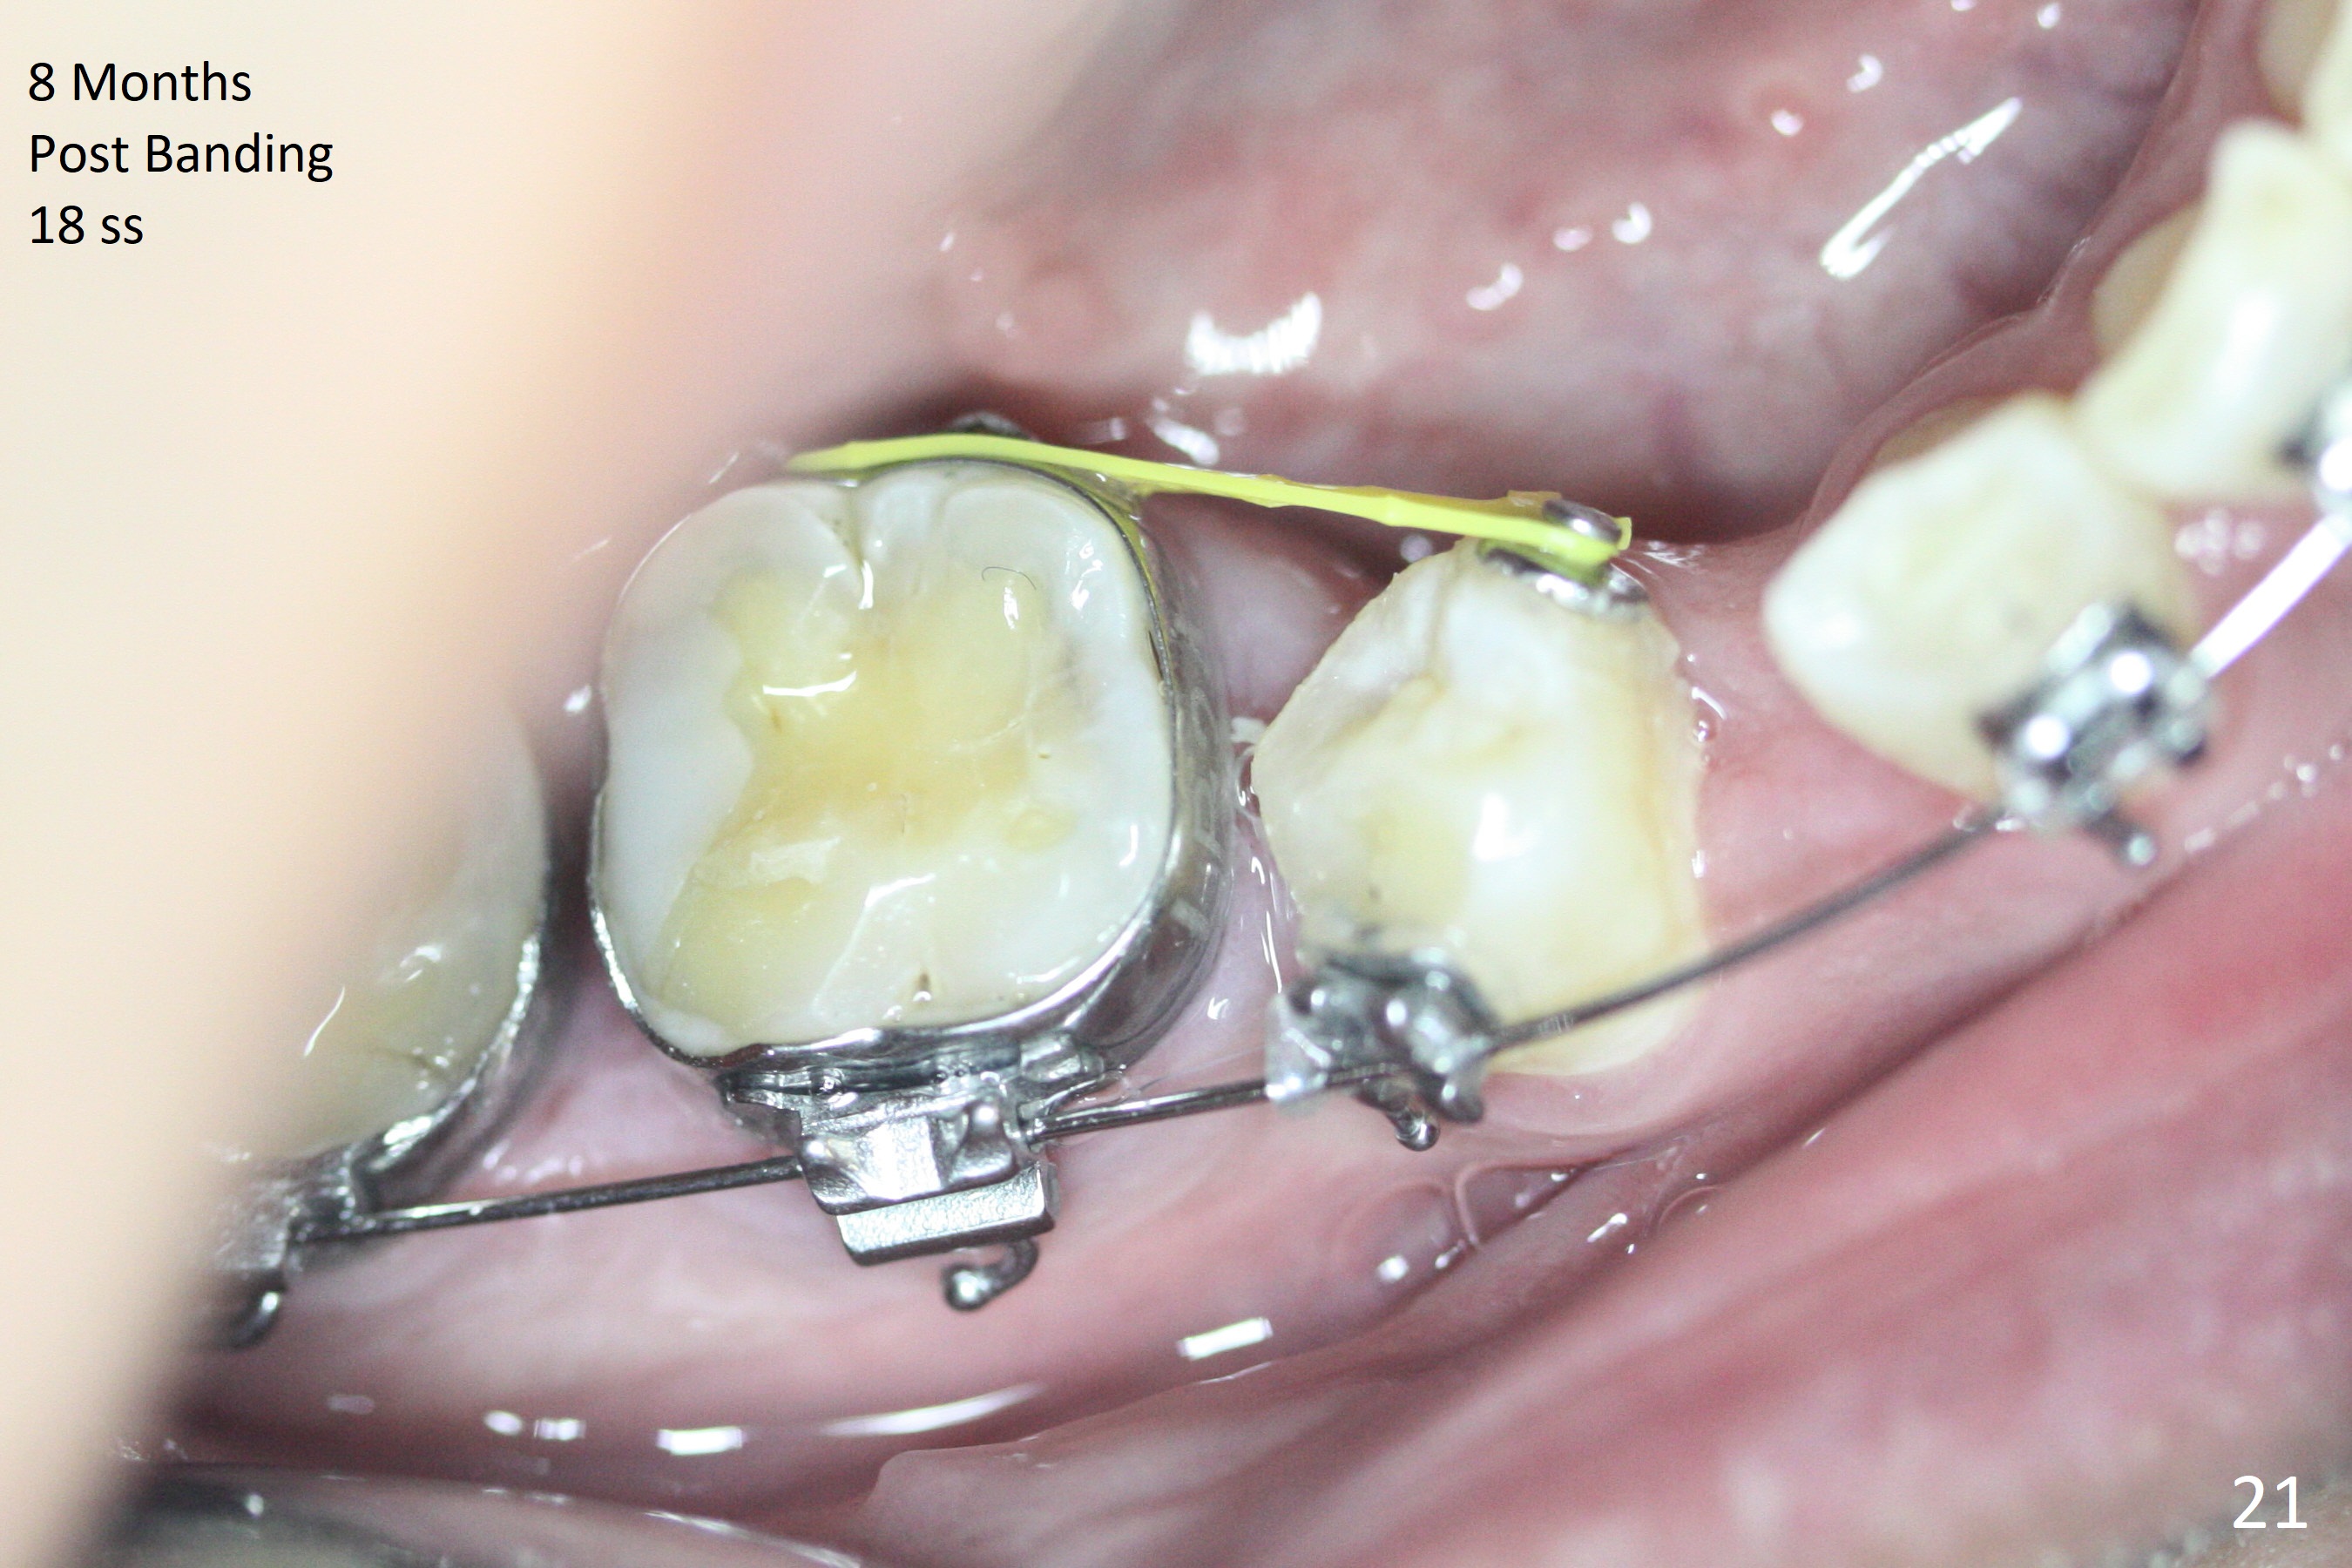

Severe crowding (Fig.1-7) appears to be alleviated especially 2 months after UR5 extraction. Diastemata seem to form mesial and distal to UR2 (Fig.8). Because of severe wear at UR3 (Fig.6), there is no bracket placement differential around it (Fig.8 (14 niti wire)). Lower bands and brackets are placed a week later (Fig.9-11). Because of tight space between LR4 and the opposing tooth (Fig.10), band adhesive is applied to L7 occlusal surface to open the bite (Fig.9). There is an abrupt kink of 12 niti wire between LL4 and 6 (Fig.11). The latter does not improve much in a month; the wires remain the same (Fig.12). For LL2, LR4 has been retracted for ~ 1 month (Fig.13). There is mild tension when 18 ss wire is inserted between LL4 and 6 five point five months post banding (Fig.14). UR4 has been distalized for a month using buccal power chains x3 resulting in rotation; to counter the rotation, a lingual button is placed with power chain x3 lingual and x2 buccal (Fig.15). With space gaining, it is time to finish definitive filling (Fig.16 *). Next visit check midlines, overjet, interdigitation, and molar classification. R4s distalize, but associate with rotation because of power chains buccal and lingual 8 months post banding (Fig.17,18). With the use of the same wires, power chains are applied lingual to continue distalization and rotation correction (Fig.20,21). Lingual buttons are placed at L2s buccalization (Fig.19) and mesialization (Fig.22,23). It appears that space should be created distal to LR3. That is that the lower anterior teeth should be shifted to the right, although it may be not appropriate for the midline.